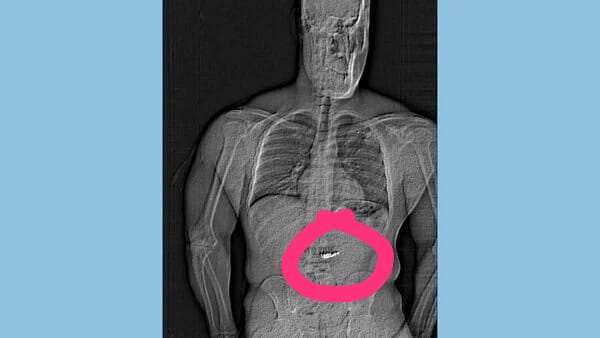

X-ray ya Polisi ya Orlando inaonyesha kitu kigeni kwenye

cavity ya mwili. Baadaye polisi walitoa picha ya x-ray iliyoonekana kuonyesha

tumbo la mtu akiwa na kitu kigeni ndani.